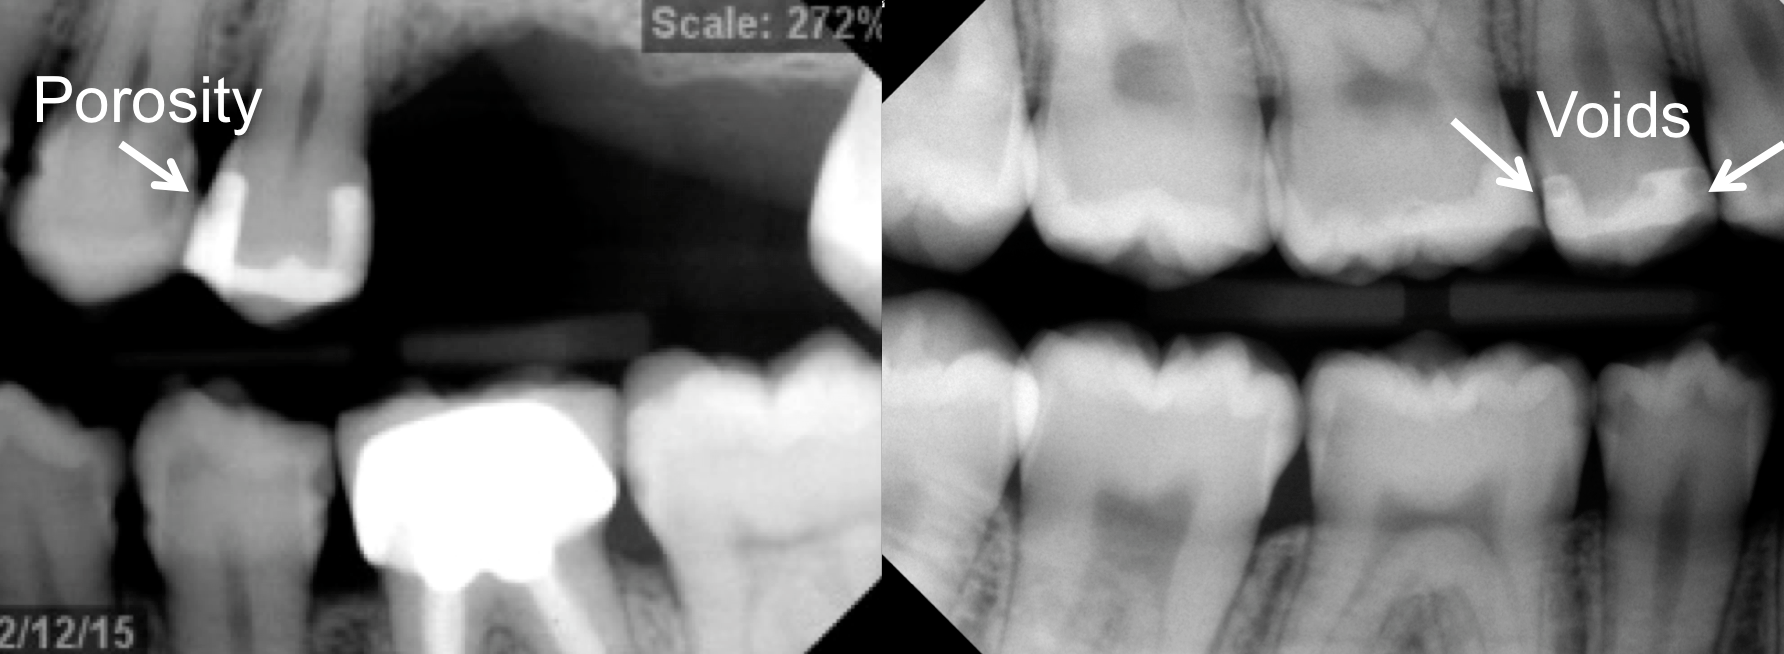

However, in the past decade, a new generation of low-shrinkage composites was developed specifically for bulk placement. These products’ advantages for placement relative to composites designed to be layered are radiographically apparent (Figure 1 and Figure 2); areas of porosity raise concerns about recurrent decay, and with a highly viscous composite, the chance of trapping air bubbles is significantly increased, compared to a dense, homogeneous void-free composite resin (Figure 2).2

Fig 1. Problems with incremental composite placement include potential voids and porosity when layering.

Figure 1

Fig 2. Radiograph shows single 4-mm incremental bulk-fill placement compared to using a layered method.

Figure 2